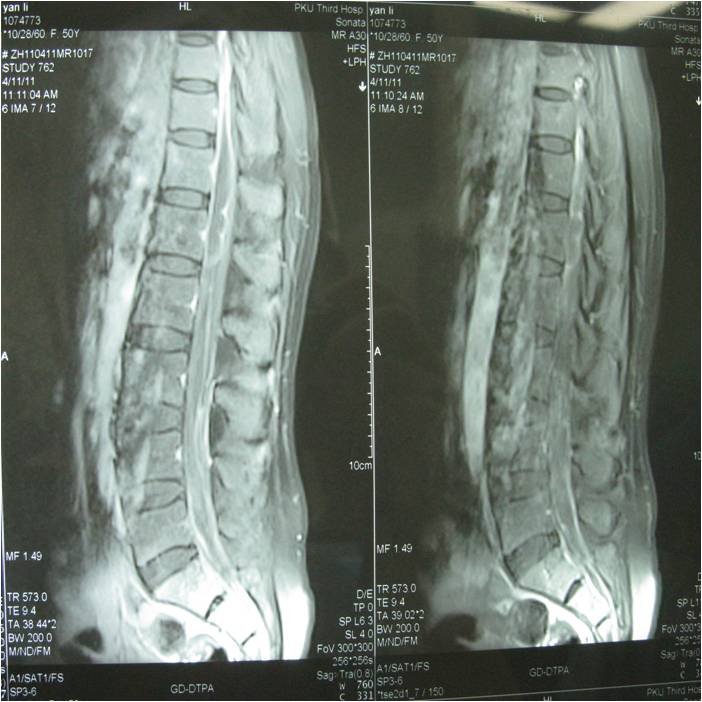

获奖病例展示---罕见全椎管脊髓囊虫病诊治